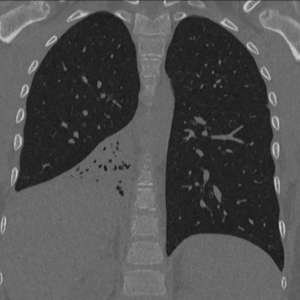

🤯 Лёгкое не дышало из-за пластикового колпачка, который жил в ребёнке полгода

Мальчика в Подмосковье лечили от «пневмонии», но диагноз оказался совсем другим.

В его бронхах 6 месяцев сидел колпачок от ручки — сам ребёнок даже не сказал об этом, пока не достали.

Удалили за полчаса. Сейчас — на поправку.